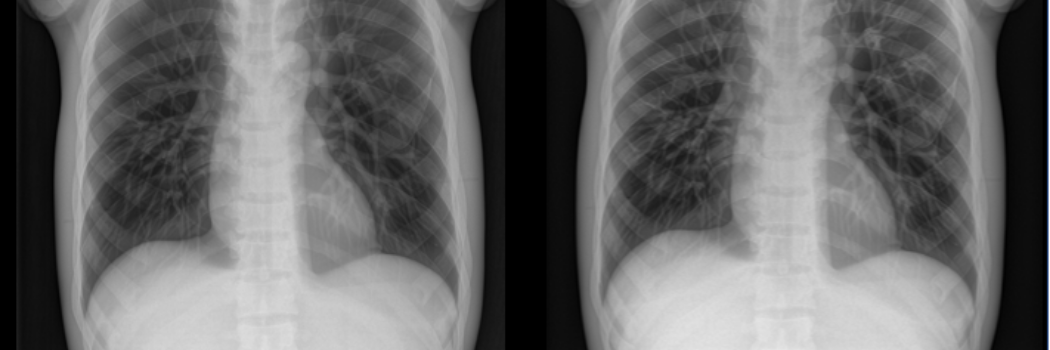

Re-defining X-ray technology

Our mathematicians have worked with industry to achieve superior quality X-ray images to support better diagnosis of patients.

Collaborating with technology firm IBEX, Durham’s experts used their statistical skills to further develop X-ray scanning technology so it can differentiate more clearly between different materials.

Bayesian approaches to X-ray imaging for material inference, dose reduction and improved image quality

Collaboration with X-ray imaging firm IBEX Innovations has produced innovative methods to improve material detection at lower radiation doses.